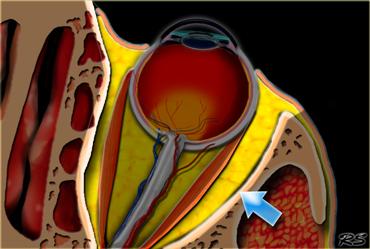

Khoang nội nón được đánh dấu bằng các mũi tên và nằm bên trong hình nón cơ. Khoang này chứa thần kinh thị giác, các mạch máu và các dây thần kinh sọ III, IV và VI.

Các cơ vận nhãn trong hốc mắt tạo thành một hình nón cơ.

Các cơ vận nhãn này được kết nối với nhau qua vòng Zinn — một tấm mô liên kết sợi — và cùng nhau tạo thành khoang nón.

Khoang nón phân tách khoang nội nón với khoang ngoại nón.

Các bệnh lý trong hốc mắt không liên quan đến nhãn cầu có thể nằm ở khoang nội nón, khoang nón hoặc khoang ngoại nón.